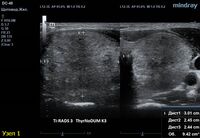

1) Узел занимает всю левую долю, но прорастает капсулу щитовидной железы (0 баллов), больше широкий чем высокий (0 баллов), не имеет кальцинатов (0 баллов), с ровным четким контуром (0 баллов), изоэхогенный (1 балл), тканевой структуры (2 балла). Количество баллов 3, ACRTi-RADS 3, ThyrNoDUMК3. Показана пункция в связи с большим диаметром узла (более 2,5см для Ti-RADS 3)